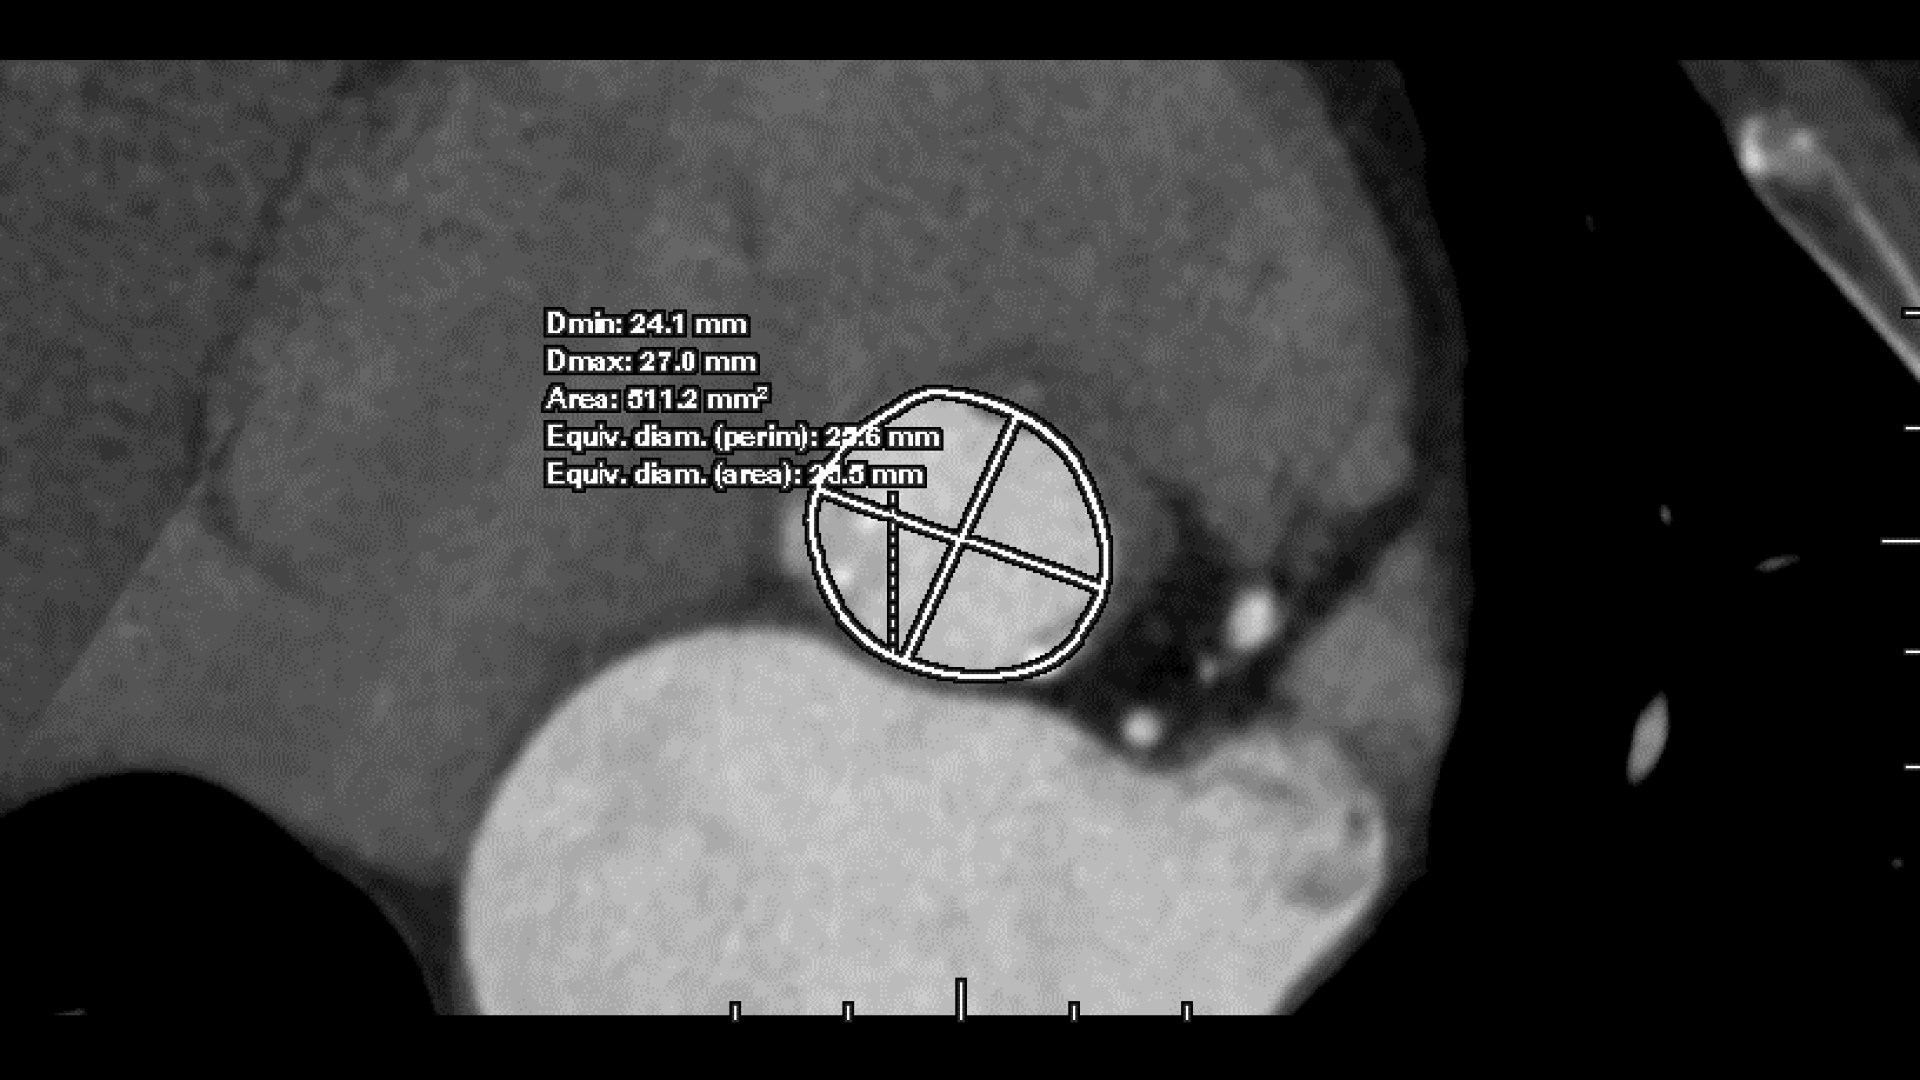

• Automated aortic segmentation and preliminary orientation to aortic annular plane

• 3-point deposit mode for precise refinement of annular plane

• >Faster valve plane detection over a manual method

Annoni AD, Mancini ME, Carlicchi E, Belmonte M, Formenti A, Mushtaq S, Marchetti F, Cilia F, Baggiano A, Fusini L, Bonomi A, Gennari M, Montorsi P, Pepi M, Pontone G.

Pre-TAVI aortic annulus sizing: comparison between manual and semi-automated new generation software measurements in operators with different experience.

Br J Radiol. 2023 Sep;96(1149):20220733. doi: 10.1259/bjr.20220733. Epub 2023 Jul 26. PMID: 37449675; PMCID: PMC10461289.